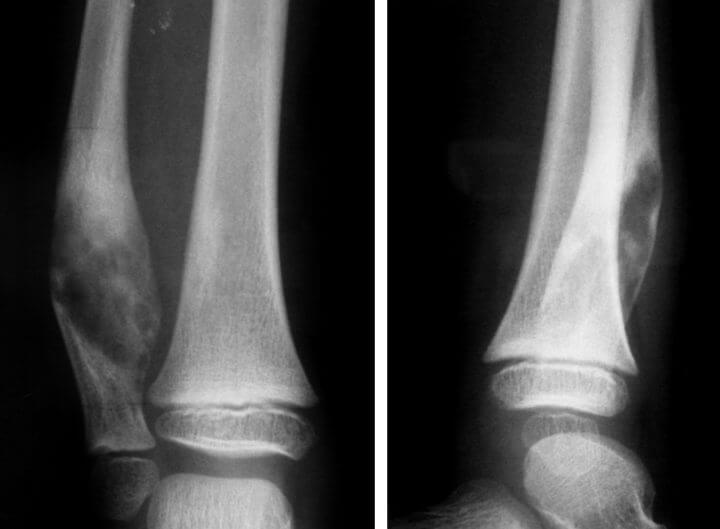

Подтвердить наличие ложного сустава можно только на основании рентгеновских снимков, КТ или МРТ. На изображениях видно закрытие костномозговой полости на концах отломков и образование замыкательных пластин. Также наблюдается суставная щель, заполненная соединительной тканью, а костные отростки становятся округлыми и сглаженными.